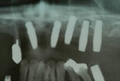

Q AQB T-type開発の背景を教えてください。 堤 AQBインプラントは、歯台部における再結晶化ハイドロキシアパタイトコーティング(以下HA) の骨伝導能による早期の骨結合で治療期間短縮を実現し、またツールを極力少なくすることで施術方法を簡素化し、仕様変更のない安定した扱いやすいシステムとして、国内有数のインプラントにまで成長しました。 1ピースタイプの発売から14 年経過し、その間にユーザーの先生から様々なご要望も届いています。 そのご要望のうち、「1ピースの術域を難症例にまで安全に拡大できたら、臨床により生かせる」という声を実現したのが、今回発売のT-typeなのです。

Q T-typeの特長を教えてください。 堤 従来のAQB1ピースを改良した形状で支台部にテーパー6°を付与しており、皮質骨と接するアバットメント部の径が約0.4 ?、通常サイズのものより太くなっています(左図) Q その改良の結果生まれたT-type固有の強みを教えてください。 堤 右表の3点がT-typeの特長でしょう。